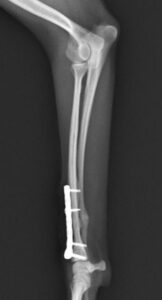

左前腕骨折のトイプードルちゃんの手術がありました。橈尺骨骨折は動物病院では一番よくある骨折です。ロッキングプレートであるTAITANコンディラー1.7mmで対応しました。治りも順調で元気に帰りました。よかったね。